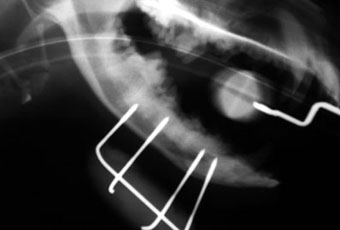

体重2.8kg、8か月齢の猫の上腕骨らせん骨折。

ピンニングと創外固定をタイインという方法で組み合わせることで、骨折部にメスを入れることなく整復固定しました。

写真上段: 手術前

写真中段: 手術直後